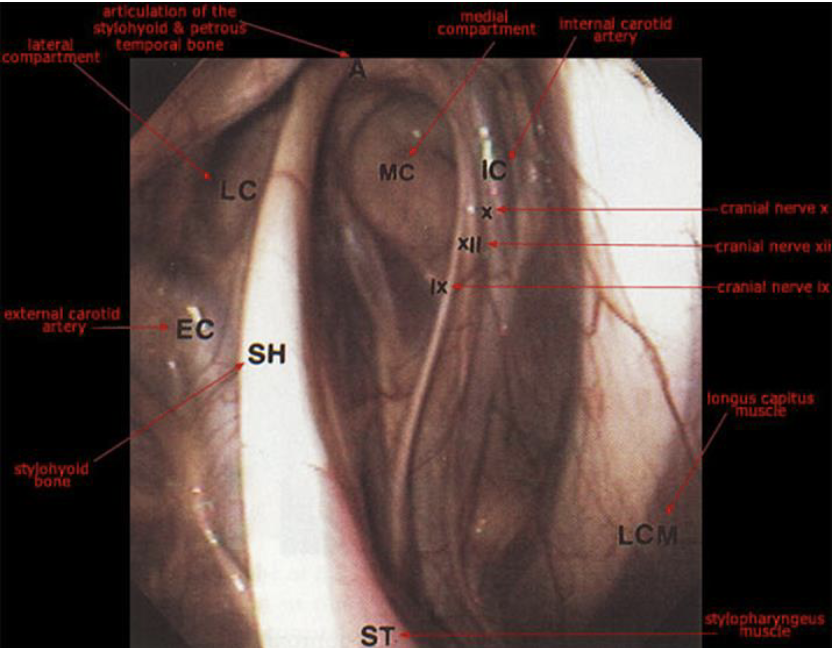

guttural pouch

what divides the guttural pouch into medial and lateral compartments

stylohyoid bone

what runs in the guttural pouch

external carotid artery (lateral compartment)

cranial nerves 9-12 and internal carotid a. (medial compartment, contained within a fold of mucous membrane on caudal wall)g

guttural pouch cranial nerves cause

9- dysphagia

10- facial paralysis

11- n/a

12- dysphagia